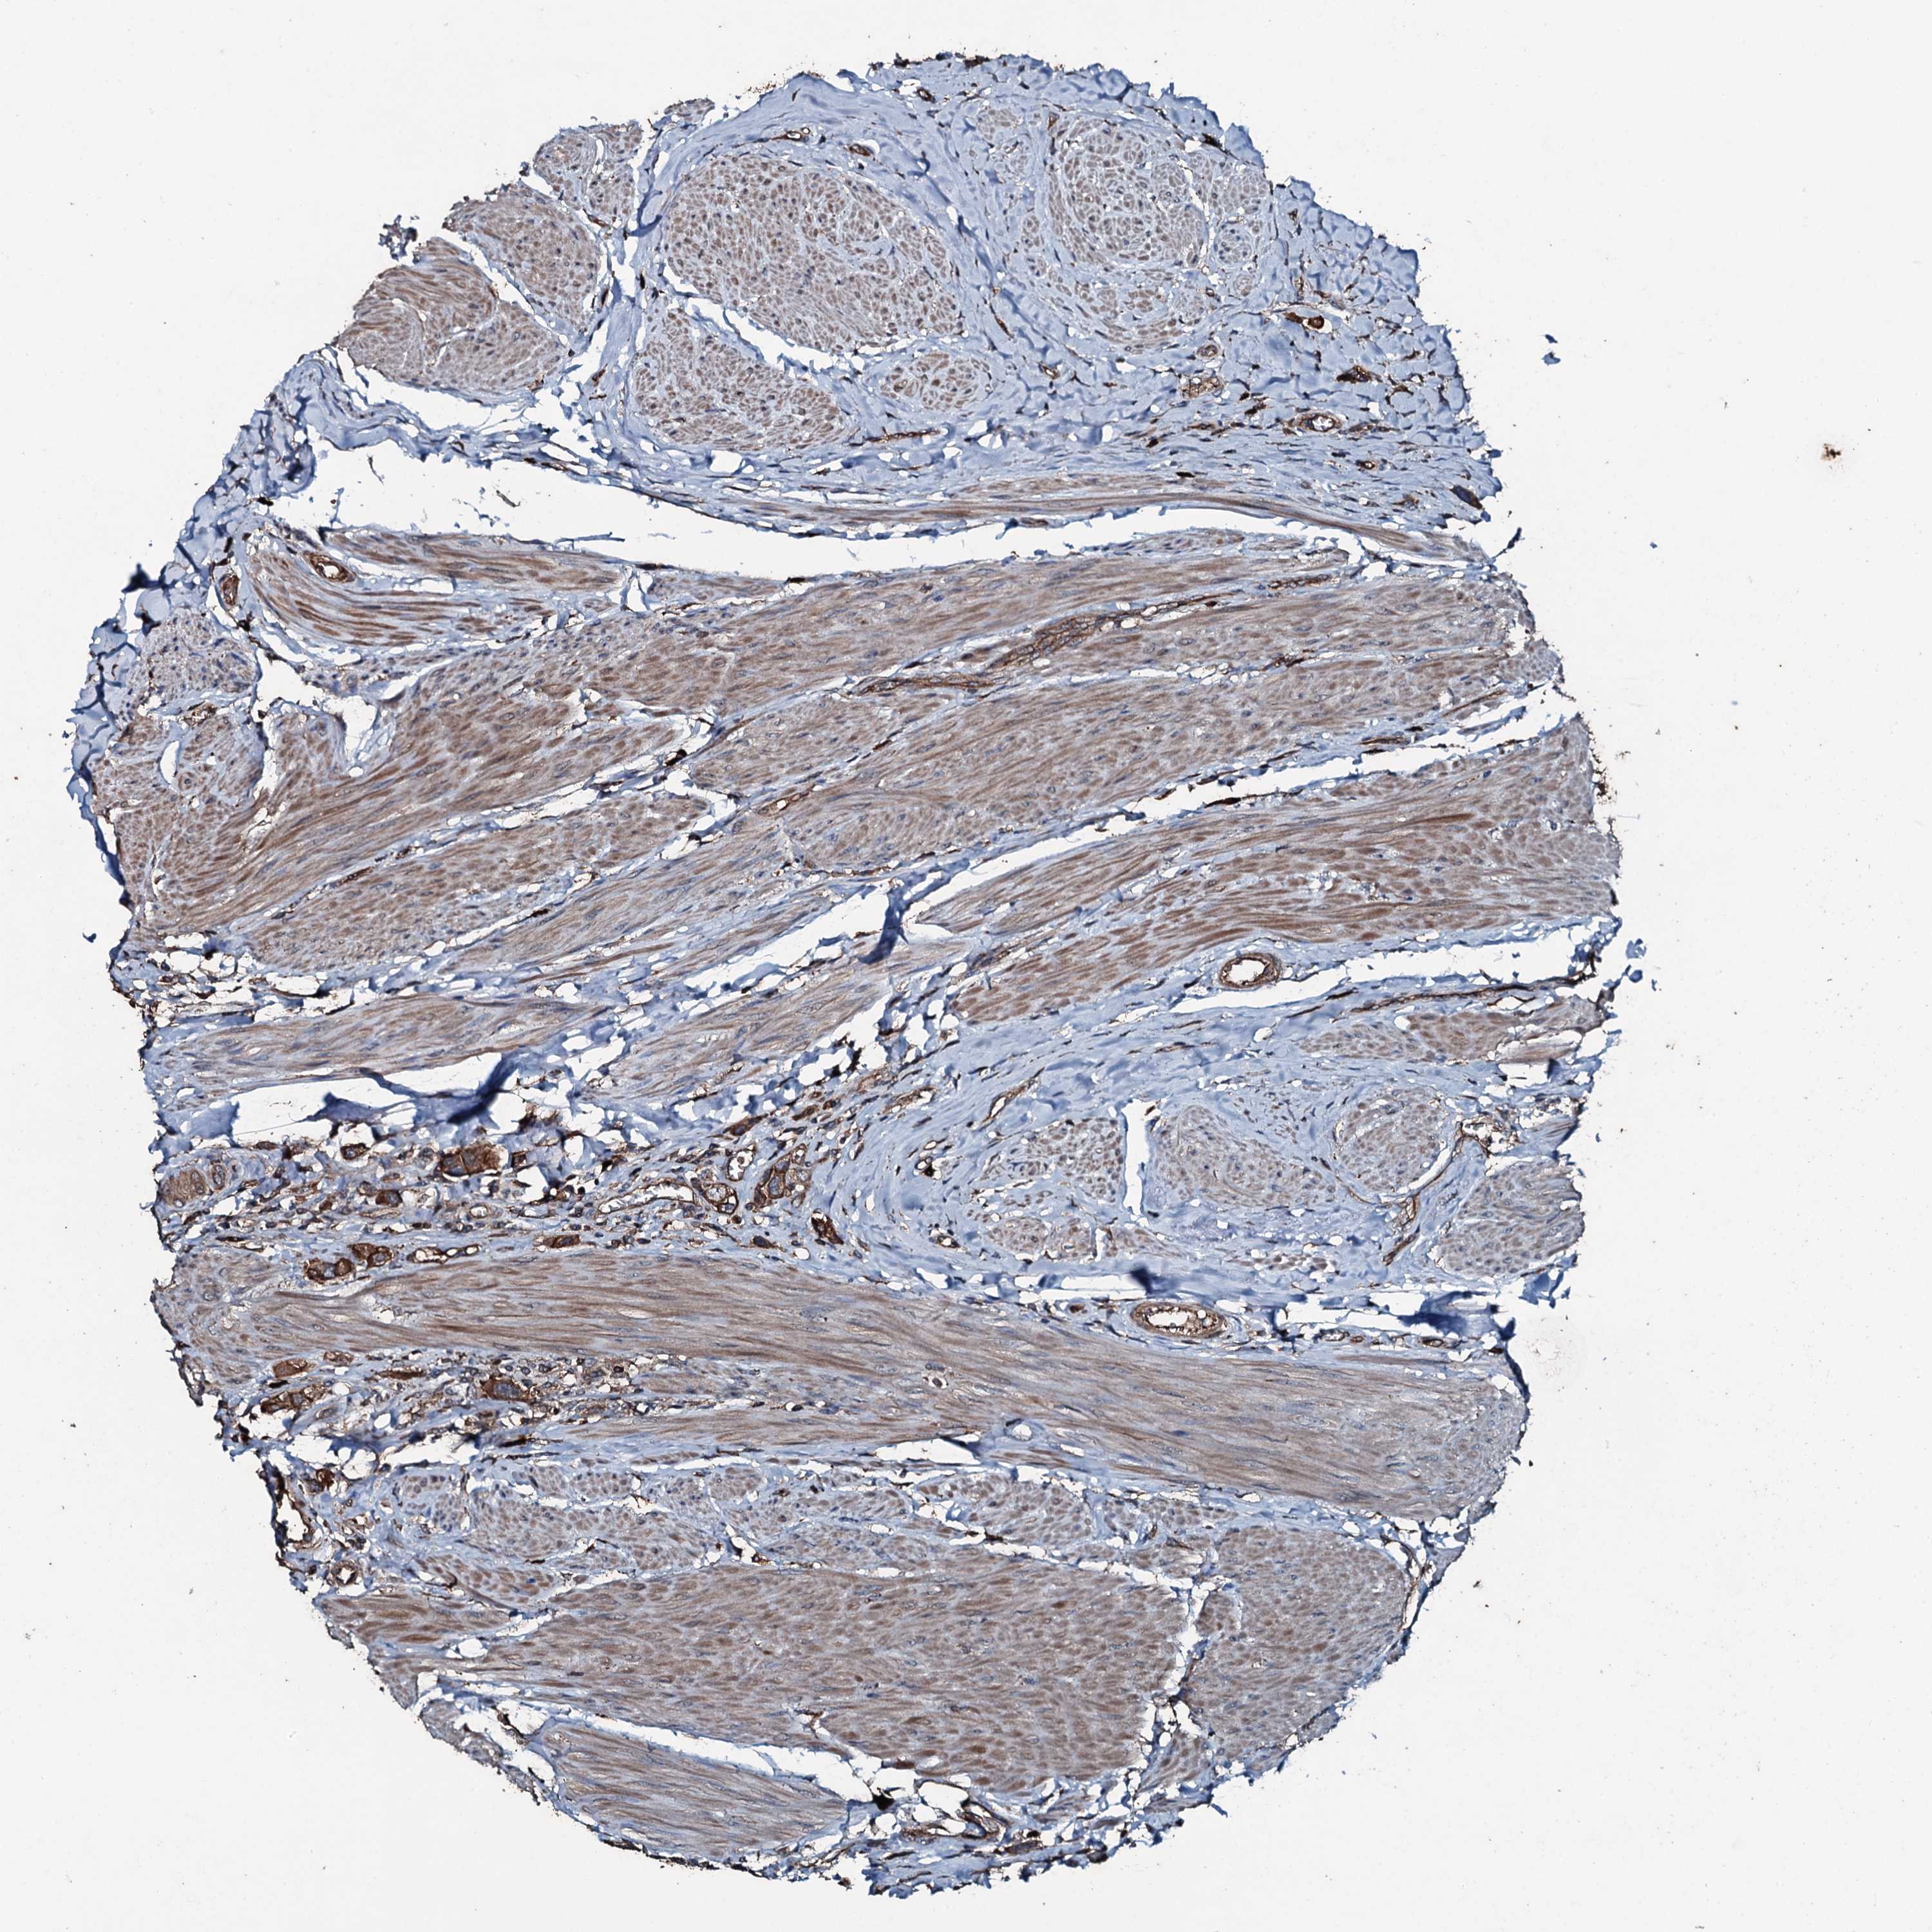

UROTHELIAL CANCER - Protein expressioni

A mouse-over function shows sample information and annotation data. Click on an image to view it in a full screen mode. Samples can be filtered based on level of antibody staining by selecting one or several of the following categories: high, medium, low and not detected. The assay and annotation is described here.

Antibody stainingi

Antibody staining in the annotated cell types in the current human tissue is reported as not detected, low, medium, or high, based on conventional immunohistochemistry profiling in selected tissues. This score is based on the combination of the staining intensity and fraction of stained cells.

Each image is clickable and will lead to virtual microscopy that enables deeper exploration of all samples and also displays staining intensity scores, fraction scores and subcellular localization as well as patient and tissue information for each sample.

Antibody HPA041027

Staining

High

Medium

Low

Not detected

Intensity

Strong

Moderate

Weak

Negative

Quantity

>75%

75%-25%

<25%

None

Location

Nuclear

Cytoplasmic/membranous

Cytoplasmic/membranous,nuclear

Urothelial carcinoma, High grade

Urothelial carcinoma, Low grade